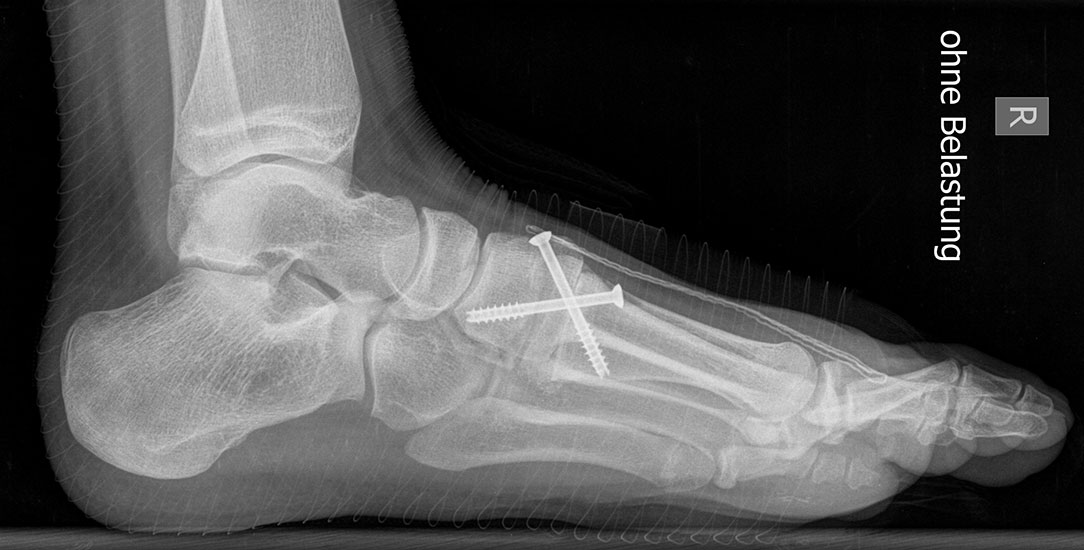

Standard ist die belastete Röntgenaufnahme des Fußes dorso-plantar und seitlich. Günstig ist eine Röhrenkippung von 10°-20°, um die Gelenke der Lisfranc-Linie einsehen zu können.

Ergänzend kann eine Schrägaufnahme hilfreich sein. Bei Metatarsalgien oder Pathologien der Sesambeine liefert die Sprinteraufnahme zusätzliche Informationen. Bei einer Pes planovalgus Fehlstellung wird ergänzend ein Saltzman view durchgeführt.